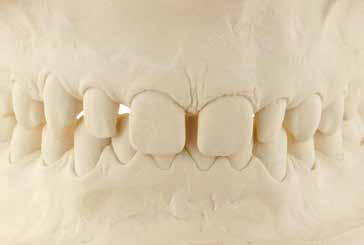

Presentazione del caso > F.V, bambino di cinque anni, presenta una malocclusione di II Classe scheletrica, III Classe dentale molare e canina destra e sinistra, morso inverso anteriore. Le arcate dentali mostrano usura degli elementi dentari anteriori a causa dell’occlusione patologica. Le linee mediane, superiore ed inferiore, sono centrate; il frenulo labiale superiore patologico per un’eccessiva estensione inter-incisale.

Il piano di trattamento prevede l’utilizzo di un dispositivo elastodontico di III Classe, da portare per due ore diurne e tutte le notti in modo passivo, senza effettuare alcun esercizio, al fine di ripristinare una relazione molare e canina bilaterale di I Classe ed il corretto avanzamento maxillare e inibire l’eccessiva crescita mandibolare. È possibile ottenere il risultato in pochissimi mesi di terapia, essendo la crescita del paziente molto attiva.

In un secondo momento, alla risoluzione della problematica scheletrica, si monitorizzerà il caso con visite semestrali in modo da reintervenire qualora si dovesse ripresentare la problematica.

Dall’esame clinico si evince la III Classe dentale, l’inversione anteriore e l’over-jet negativo.

Una volta ottenuta la correzione del rapporto molare ed incisale, l’apparecchio elastodontico verrà portato dal paziente solo durante la notte per stabilizzare il risultato ottenuto e guidare l’eruzione degli elementi dentari per un totale di quattordici mesi di terapia. ad inizio trattamento :

Considerazioni > L’analisi cefalometrica ad inizio trattamento dimostra la II Classe scheletrica con protrusione del mascellare superiore e prognazia mandibolare; tendenza alla crescita verticale. L’esame clinico evidenzia una protrusione mandibolare funzionale.